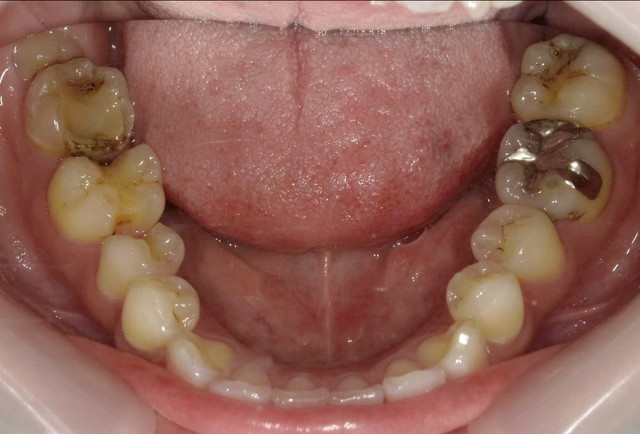

■治療前(下の歯)